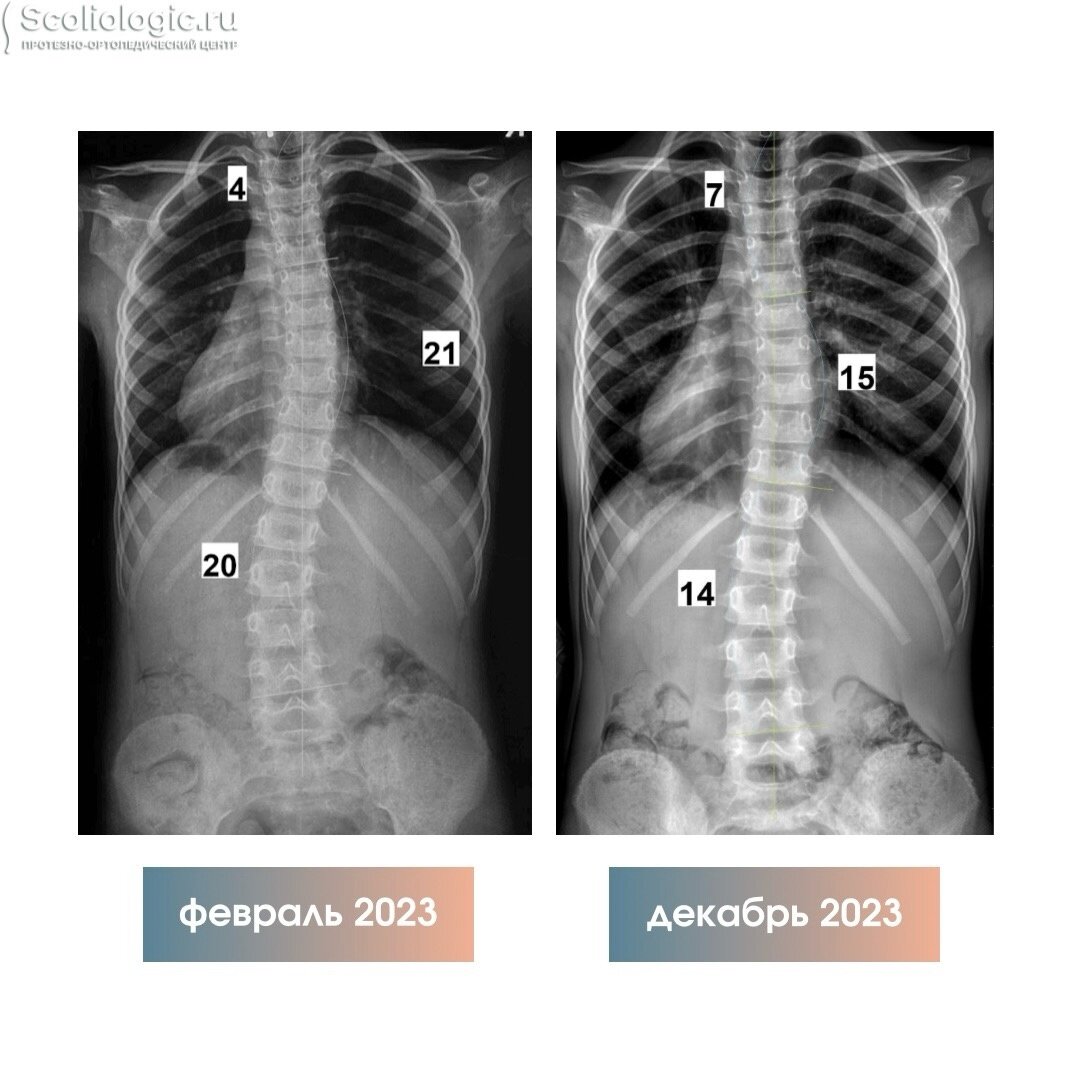

Мария Федоровна сократила комплекс упражнений, и он стал занимать около 30 минут. Рентген спустя 7 месяцев показал положительный результат.